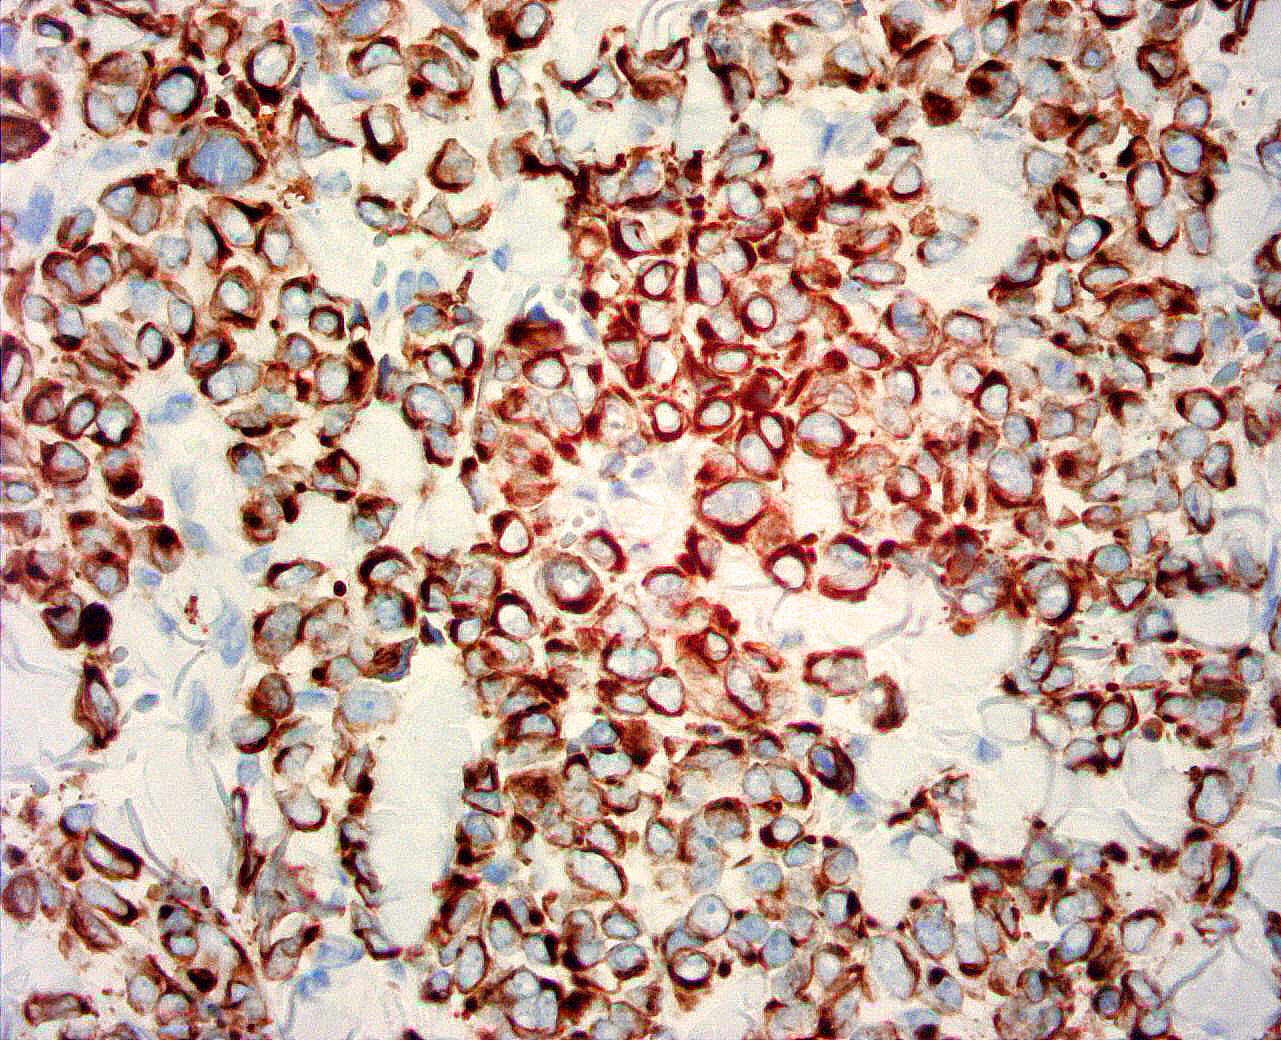

Dermatopathology

• Immunohistochemical and special stains on-site, further enhancing timely turnaround of more complex cases